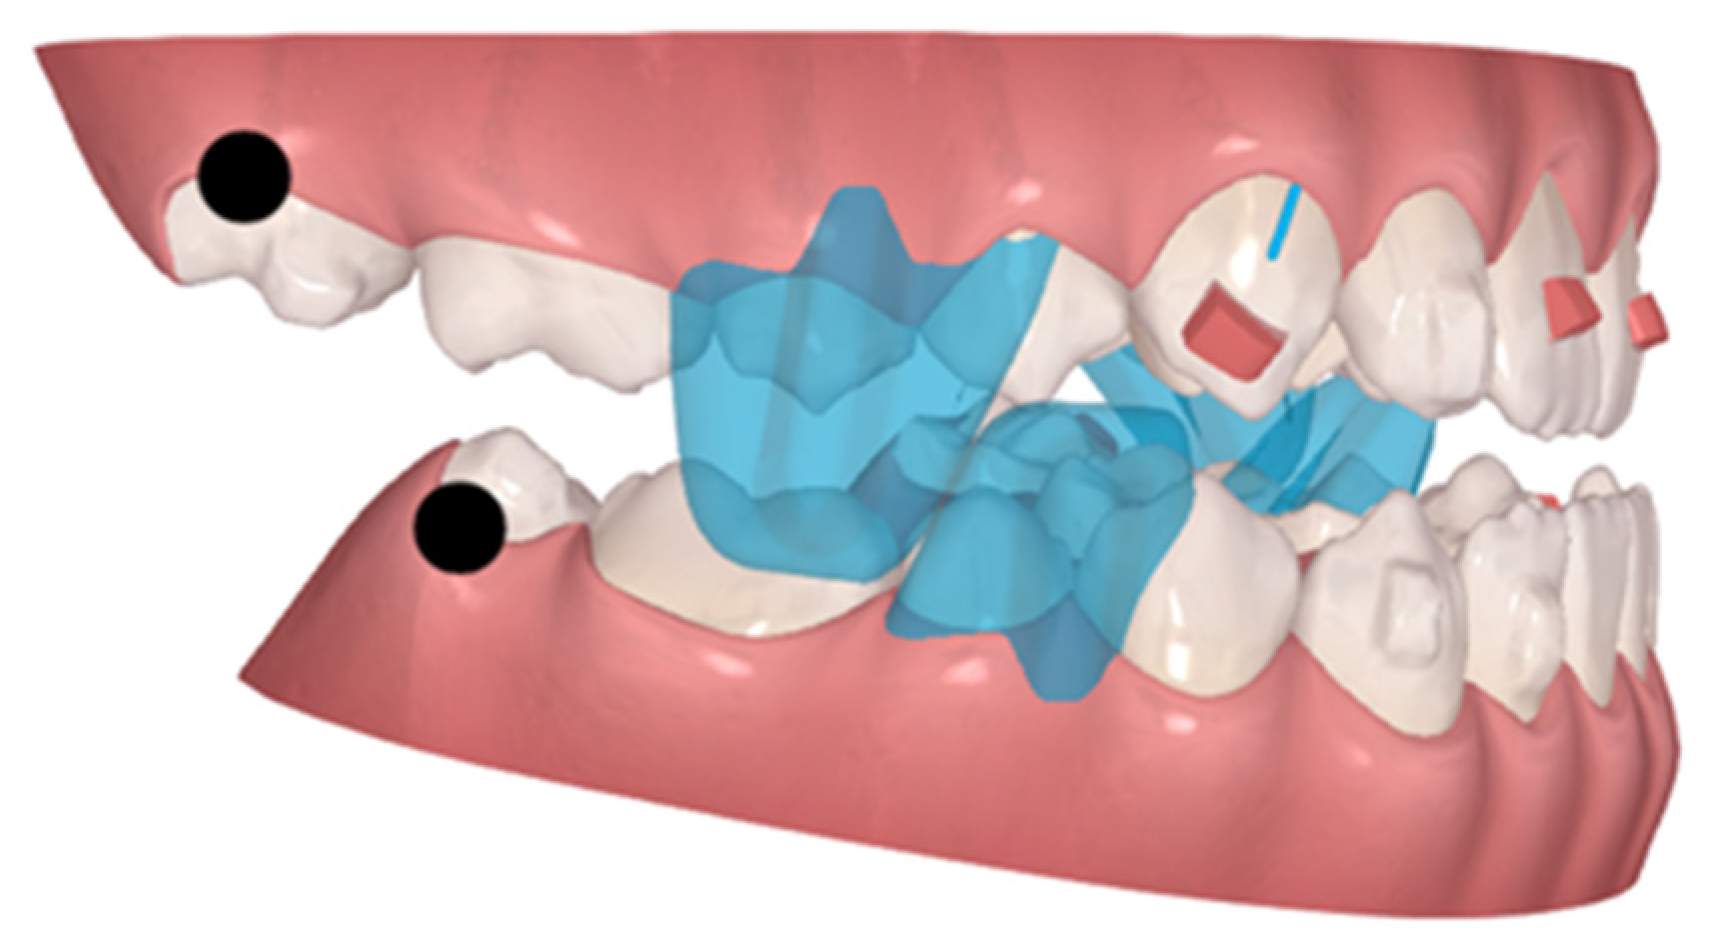

2.2. Treatment Progress